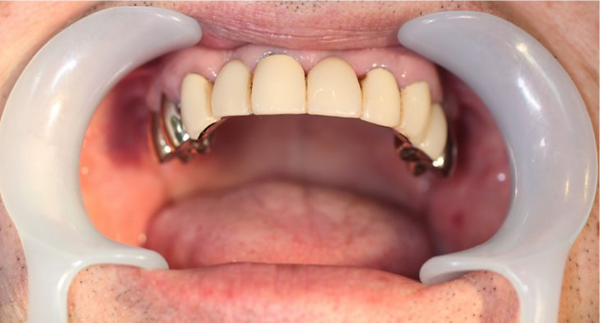

6入れ歯にしないブリッジ治療【ケース1】

H20.6.2のレントゲン

歯槽膿漏の為、上の6本の歯を抜き、上の右端から左端まで繋げたブリッジを作りました。

H31.1.25のレントゲン

H21.2.21に上の歯(ブリッジ)が完成しました。

左の写真は10年ちょっと経過したH31.1.25日に撮影した写真で、経過良好と思われます。

下顎も虫歯と歯槽膿漏のため長く持たせるために左下奥歯の一本を抜歯し残りを繋げて作りました。